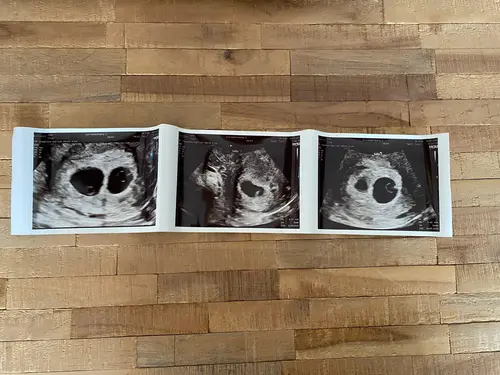

Wat een mooie echo zeg! Snap heel goed dat je even flink bent geschrokken, hopelijk went het idee snel!

Hier ook in shock! De zwangerschap was al een complete verassing. En hier ook meteen 2 vruchtzakken in beeld met 2 kloppende hartjes. Nu gemeten op 7 wk en de andere op 7+ 3 wk. Voor ons word het dan nummer 5 en 6 🤭